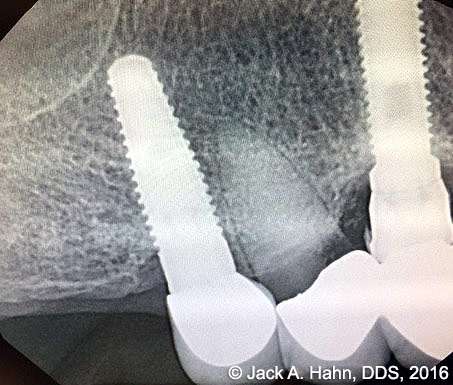

CASE #4 Trauma Case – Central Incisors Internal / External Resorption

Implants, that replace failed endo- or perio-compromised teeth, have a MUCH higher success rate with laser decontamination of the osteotomy site. LightScalpel laser surgical and perio laser tips ensure excellent access to extraction socket for the optimum removal of granulation tissue and socket decontamination (protocol involves manual curettage of the socket with alternating rinsing and lasing).

The patient, a 17-year-old female was involved in a water slide accident 3 years ago. As a result, both central incisors were avulsed and an endodontist replanted them. Both teeth exhibited internal and external resorption. Dr. Hahn extracted both central incisors, removed all the root fragments and sanitized the sites with the LightScalpel laser which also eliminated any granulation tissue. The #8 area was prepared to place a Hahn 4.3×13 Implant and #9 was prepared for a Hahn 3.5×13. 3mm tall Hahn healing abuts were placed slightly below the gingival-tissue level to help develop an emergence profile when at the restoration time in 4 months. Upon seeing the x-ray, Dr. Hahn tightened the healing abutment on #9 to be sure that it was completely seated on the implant. 45nucm. stability was achieved on both implants. He then placed some bone putty to seal any openings. To be on the safe side, he decided to place a temporary partial instead of immediate temporary prosthetics.